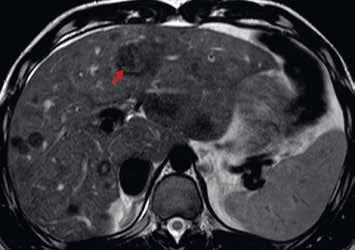

U pacientů s velkými regenerativními uzly vidíme hypervaskularizované ložisko či ložiska, jejichž sycení přetrvává i do portální fáze vyšetření (obr. 13–19). V nativním MR obraze jsou patrná ložiska – v T1-váženém obraze hyperintenzní a v T2-váženém obraze izointenzní či heterogenně intenzní.

Již nativně jsou na T1-váženém obraze vidět vícečetná hyperintenzní ložiska (7). V arteriální fázi ložiska zůstávají hyperintenzní (8), v portovenózní fázi (9) a v hepatospecifické fázi (10) postupně splývají s okolním parenchymem.

Nativně je v jaterním parenchymu naznačeno několik minimálně hyperintenzních ložisek (13). Ložiska se zvýrazňují ve fázi arteriální (14) i portovenózní (15). V hepatospecifické fázi jsou nadále hyperintenzní (16).